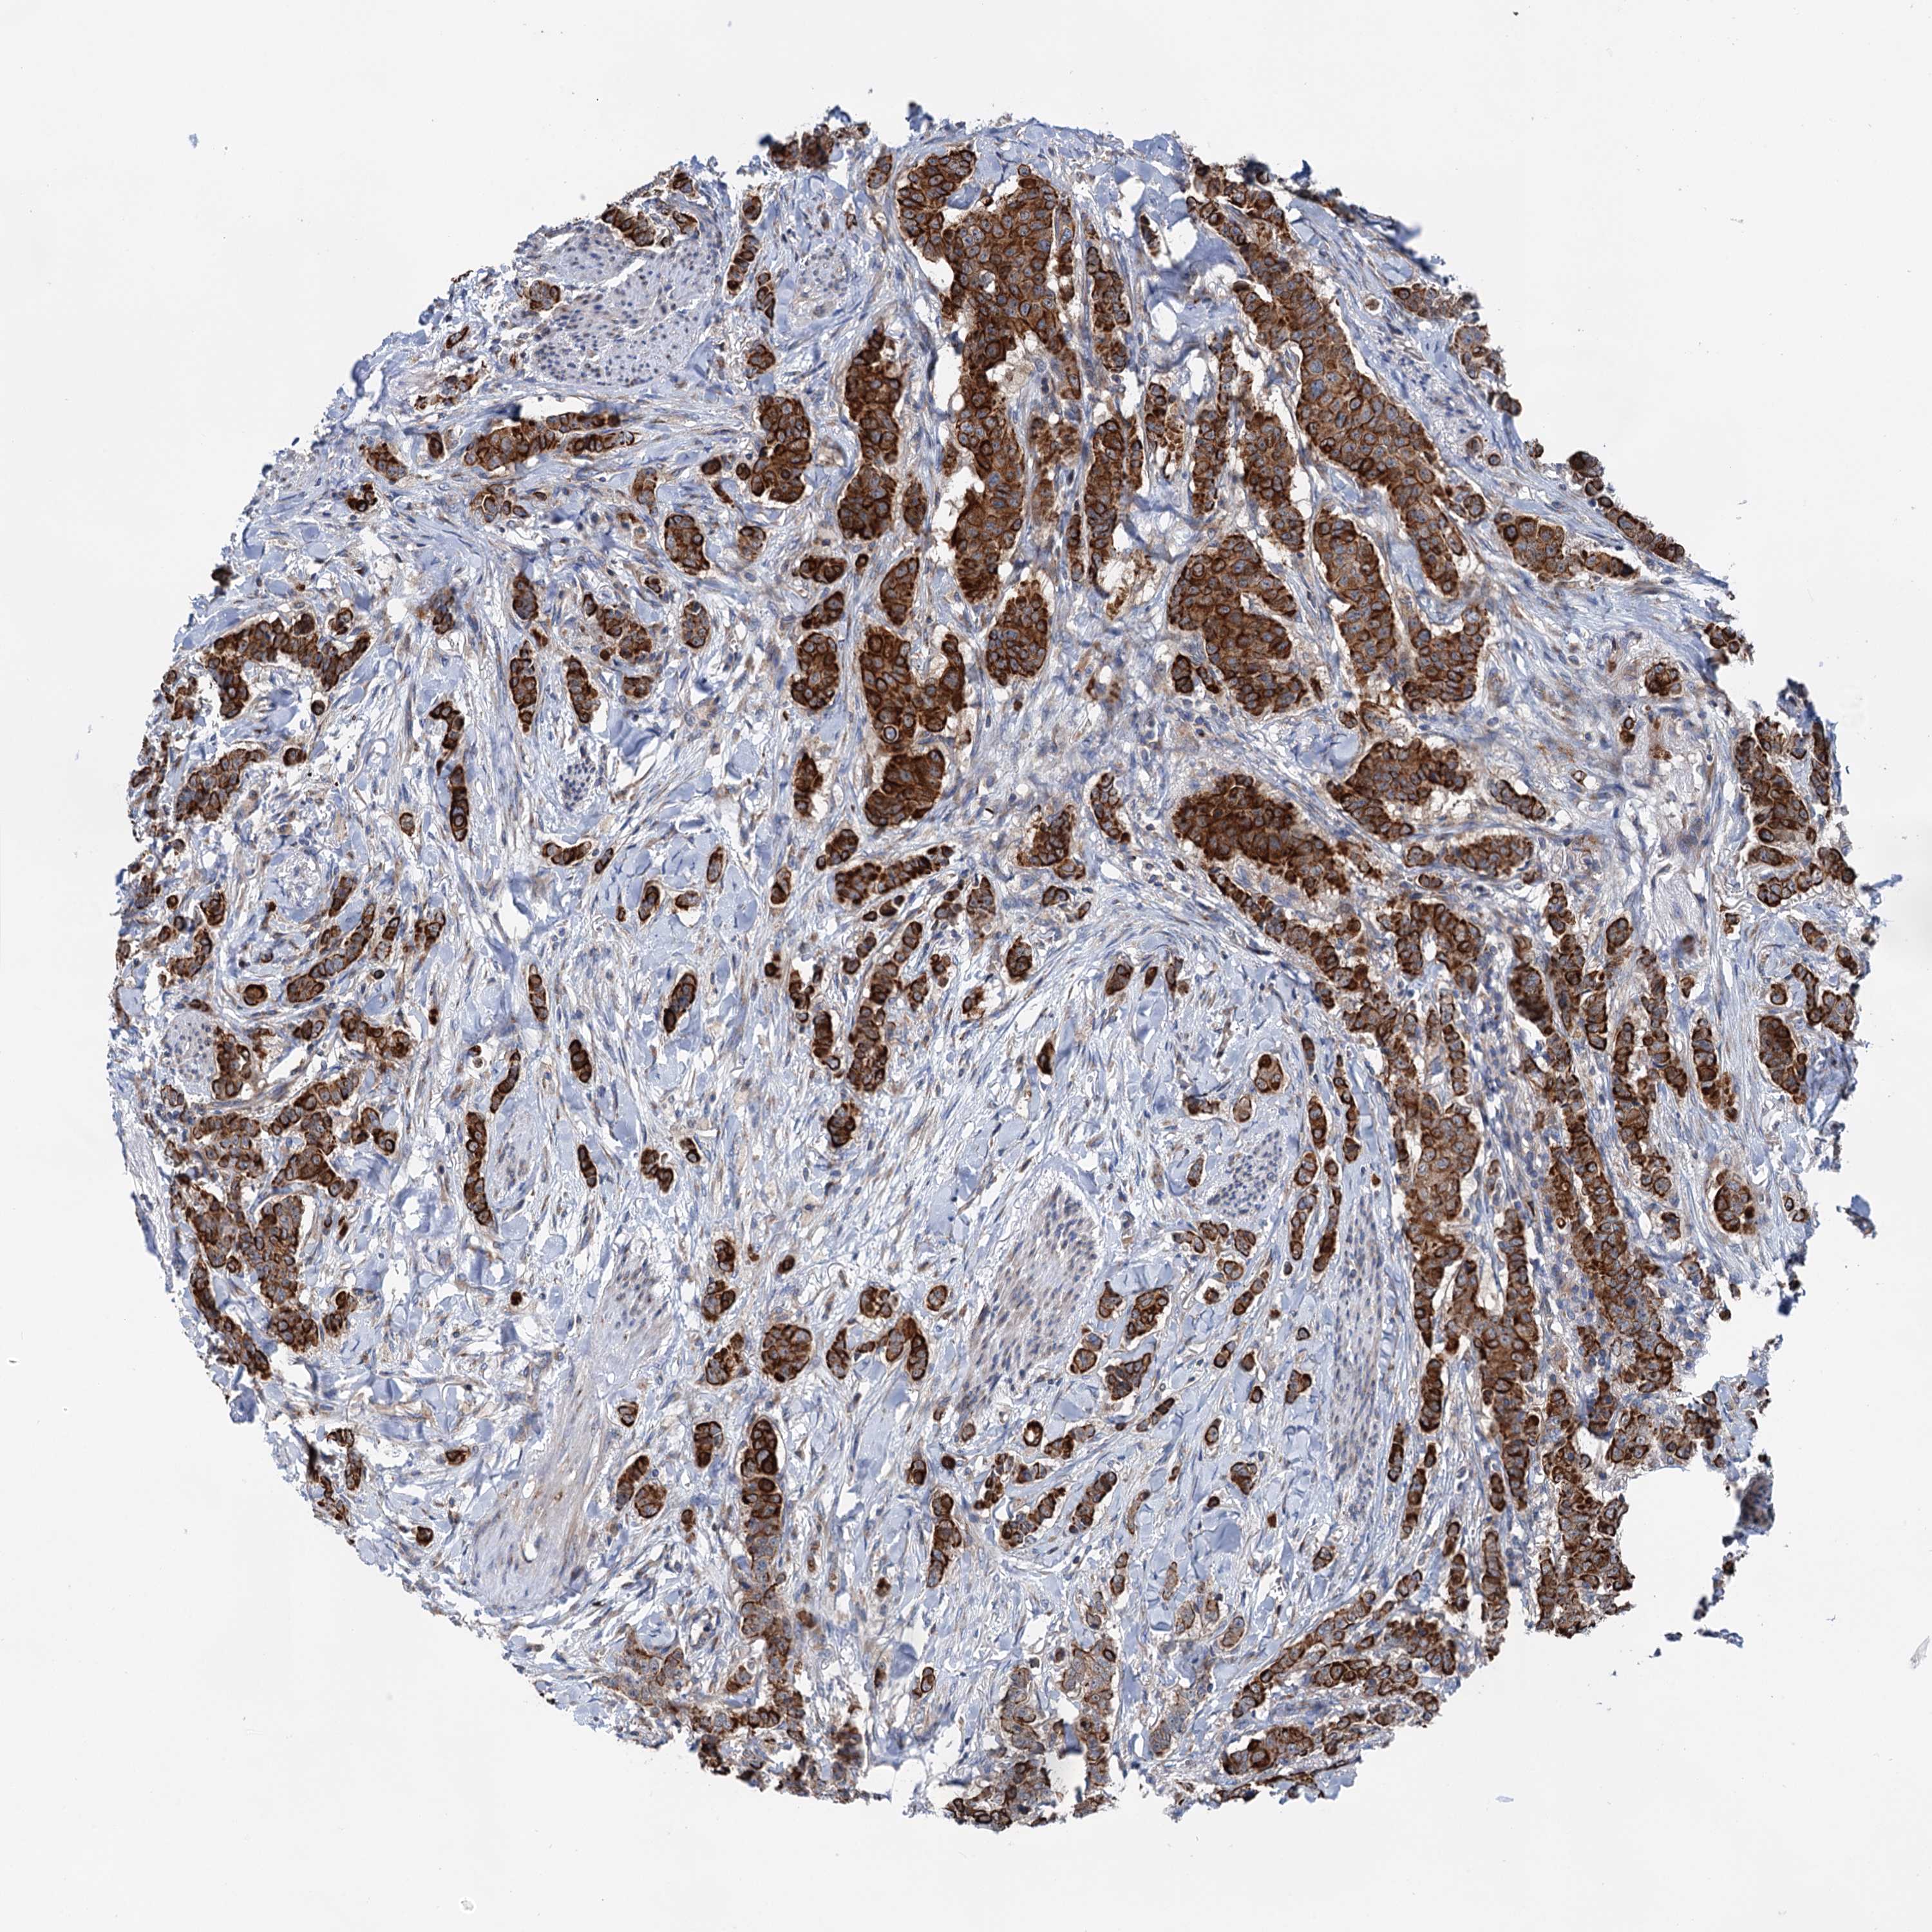

CANCER BREAST CANCER Show tissue menu

BRCA TCGA BRCA VALIDATION PROTEIN EXPRESSION